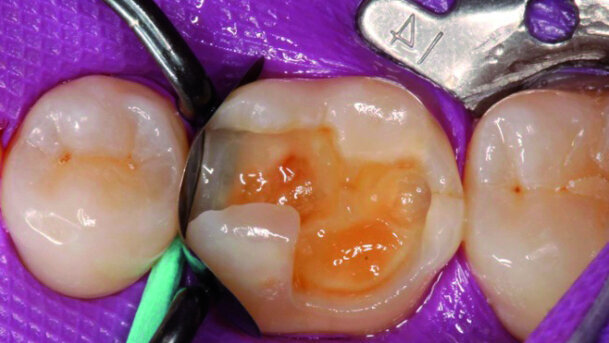

Le patient de 48 ans a été traité il y a six mois avec une obturation avec Biodentine (Septodont) à la 2ème prémolaire supérieure droite 15 (Fig. 1). L’obturation provisoire va maintenant être remplacée par une obturation permanente. L’excavation suivante de la cavité occluso-mésiale très profonde a été possible sans aucun problème ; une ouverture de la pulpe a pu être évitée en utilisant cette approche à deux étapes. La figure 2 met en évidence la cavité avec la matrice sectorielle LumiContrast (Polydentia) en combinaison avec l’anneau associé sous l’isolation d’une digue dentaire en caoutchouc (Rubberdam). Cette matrice sectorielle extrêmement stable et donc « infroissable » peut être facilement manipulée et positionnée dans la zone de contact. Un avantage de ce système de matrice porte sur la couleur presque noire qui a été obtenue en utilisant un procédé de coloration spécial (sans revêtement !) pour la feuille métallique. Cela produit un contraste exceptionnel dans la transition vers le tissu dur de la dent et facilite l’inspection du scellement cervical (aucune perturbation causée par les réflexions dans le film métallique). Un coin en bois classique a été utilisé de façon cervicale afin de serrer la marge cervicale à ce niveau.

L’anneau de séparation LumiContrast peut être utilisé dans deux versions, tout d’abord comme illustré sur la figure, correspondant à un anneau de séparation classique en argent. Cependant, il y a également la possibilité de placer de petits ergots triangulaires en silicone pour permettre un meilleur scellement interproximal des côtés, car ils permettent de mieux presser les films de matrices sectorielles sur les côtés des surfaces de préparation interproximales. Ceci n’était toutefois pas nécessaire dans le cas présent. La figure 3 met en évidence la cavité conditionnée avec le gel d’acide phosphorique ; la figure 4 met en évidence la surface adhésive scellée avec un adhésif classique à deux flacons (Optibond FL, Kerr). La restauration a été construite à partir d’un nanocomposite hybride (Venus Diamond A3, Heraeus Kulzer, Hanau, Allemagne) en utilisant une technique d’apposition de couches obliques (Fig. 5). La figure 6 met en évidence la même dent lors d’une autre visite de suivi, un an après.